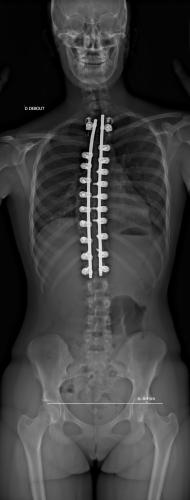

Images de scolioses opérées 16 janvier 202418 janvier 2023 par Damien Scoliose Thoracique 1 Radiographie pré-opératoire de Face Radiographie pré-opératoire de Profil Radiographie de Face à 3 mois post-opératoire Radiographie de Profil à 3 mois post-opératoire